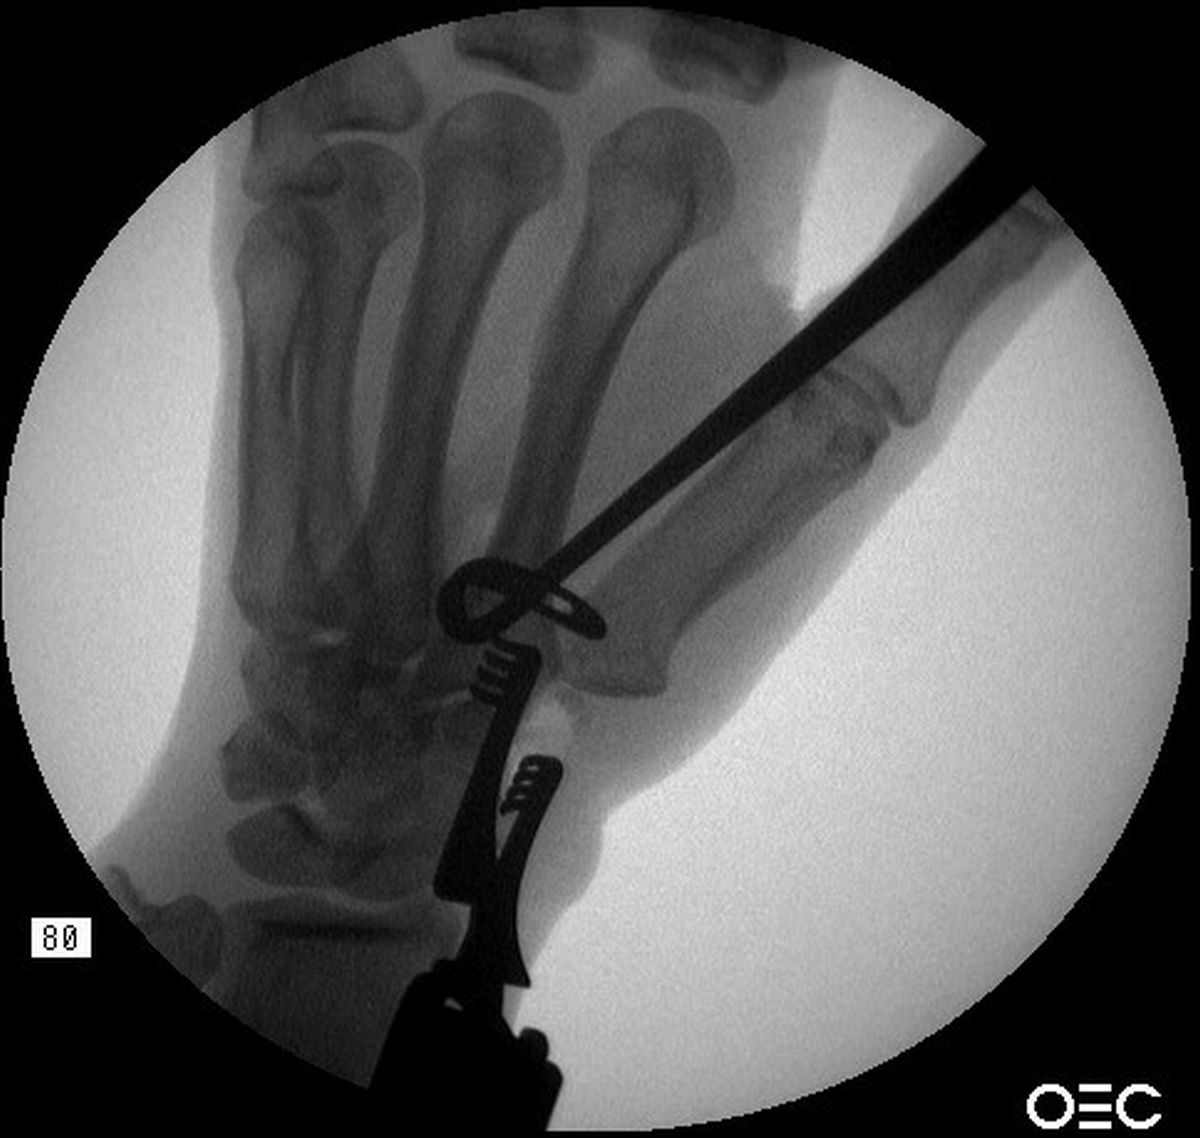

| Summary: after

trapeziectomy, a slip of abductor pollicis longus tendon is passed

around the base of the index metacarpal and sutured to itself proximal to the metacarpal base. |

| This technique allows a

strong distal force vector, and care mist be taken to avoid

overdistraction. |

| 8 months postop. The

trapeziectomy defect height is still maintained. |